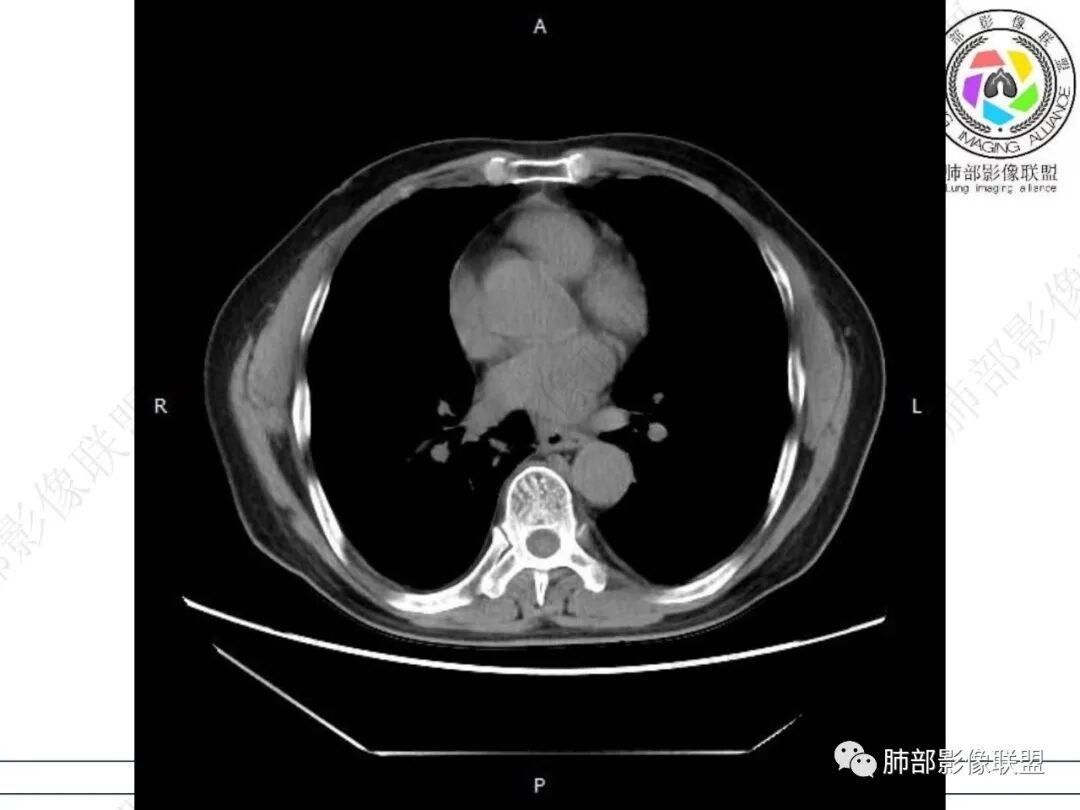

气管隆突下团片影,其内积气,与食道分界不清,食道壁增厚,管腔狭窄,右下肺实变影,支气管壁增厚,考虑食管支气管瘘并右下肺感染,食道肿瘤病变不除外

支持食管支气管瘘(考虑食管癌)伴后纵隔及右肺感染,食管管壁明显增厚,管腔狭窄,相邻右侧后纵隔内软组织内可见气体影,与食管分界不清,右肺有实变及不张。

老年男性,慢性病程,右肺下叶斑片影、斑点影、实变影,支气管轻度扩张,病灶整体稍收缩;食道壁增厚、肿胀、模糊,气管隆突及右后纵隔旁见软组织块影,其内见气泡影,均匀强化,符合食道支气管瘘伴周围炎症,右下肺炎症

右肺下叶沿肺叶肺段分布斑片、条片状影,以下叶背段为显,边缘模糊,内可见支气管走行,局部支气管管壁增厚,右侧胸腔少量积液。纵隔隆突下可见不均匀软组织密度影,与周围结构分界不清,内见气体密度影,与食管及相邻右肺支气管之间未显示通道。邻近食管下段壁明显不规则增厚,增强后食管管壁明显不均匀强化,可见线样强化的连续完整粘膜影。

对比患者3月份的CT图,原隆突下存在增大钙化淋巴结,现在出现气体影,且钙化显示不清,应想到淋巴结结核破溃成瘘可能性。